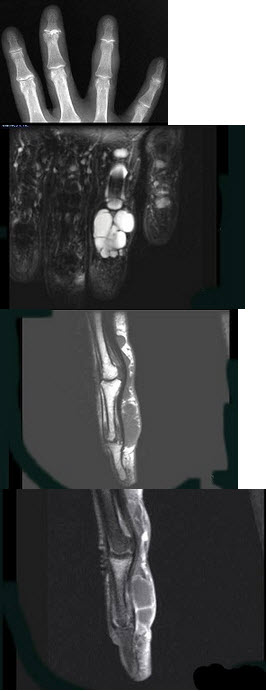

62、单项选择题

男,15岁,从楼梯上滑倒,足部扭伤,结合图像,最可能的诊断是()

A.腓骨骨折

B.胫腓骨骨折

C.胫骨骨折

D.距骨骨折

E.跟骨骨折